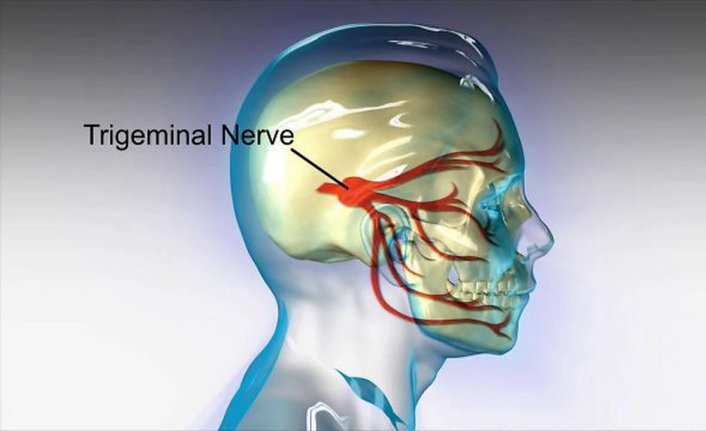

Trigeminal nevralji, yüze vuran, kısa süreli "şimşek çakar" tarzda ağrılardır.... Devamı

Annem 10 yıldır trigeminal nevralji hastası. Demediğimiz hiçbir tedavi kalmadı. Bloklama,radyoterapi, nöralterapi defalarca yapıldı. Ancak bu tedaviler geçiçi olarak ağrıyı yok ediyor ve ağrıları şiddetlenerek geri geliyordu.Artık yemek yiyemez,konuşamaz olmuştu.Seçeneklerimiz arasında ameliyat hiç yoktu.Ta ki doktorumuz Kagan Beyle tanışana kadar.Güven veren ve samimi yaklaşımıyla annemi ameliyat olmaya ikna etti.Gercekten cok nadir yapilan ve o kadar da zor olan bir ameliyatti. Bu alanda gercekten bilgisi ve tecrubesi ile en iyilerden biri olan hocamiz Sayin Prof.Dr.Kagan Tun cok basarili bir Mikrovaskuler Dekompresyon ameliyati gerceklestirdi.Annem iki gun yoğun bakımda kaldiktan sonra bugün servise alındı.Nevraljiden kaynaklanan ağrıları bıcakla kesilmiş gibi bitti. Şuanda sadece ameliyattan kaynaklanan olağan baş ağrısı var ve zamanla azalıyor.Degerli hocamiza, ekibine ve Eskisehir Acibadem Hst. Personeline yürekten tesekkur ediyoruz...